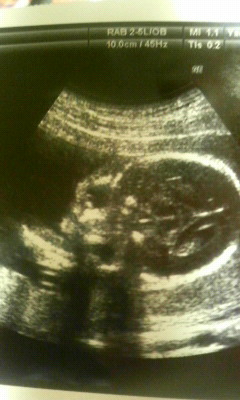

12月22日は妻の診察日であった。現在、妊娠6ヶ月のお腹は大分出てきている状況だ。

いつも通り先生が超音波でお腹の様子を診てくれた。そしてモニターに映し出された赤ちゃん(そら)は素人の私が見ても分かるくらいに成長していたのである。頭部の直径は6cm、頭からお尻までが14cm、重さが377gあるという。明らかに大きくなっている。

先生に性別を聞いてみたところ、「うーん、多分女の子かな」と仰った。どうも8割がた女の子のようである。なんとも嬉しいものだ。

続いて先生が違う映像を見せてくれた。なんと4D映像という。映像を見てみると、鮮明に顔の様子が映っていた。医療技術も明らかに発達していると実感した。